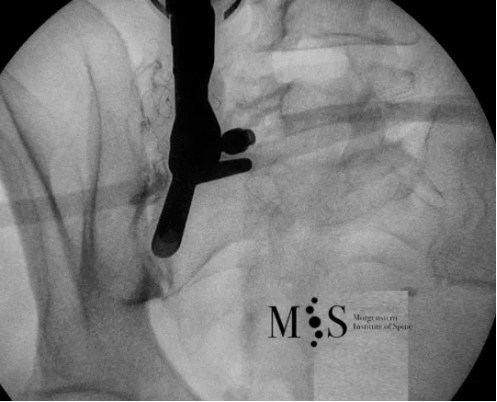

Example of an intra-articular infiltration of the right sacroiliac joint

Dr. Morgenstern performs intra-articular infiltrations of the sacroiliac joint using a new intra-articular infiltration technique developed in German that allows the joint to be infiltrated on an outpatient basis, without the need of contrast medium and operating room (which are usually necessary for other, popular infiltration techniques).

The analgesic effects of the SI joint infiltration are usually immediate. Still, two infiltrations are usually recommended with a time interval of 2 to 3 weeks in order to significantly reduce inflammation of the affected sacroiliac joint and decrease the pain for a long period of time.

This is an intra-operative picture showing an endoscope

(at the left side of the picture) placed directly on the right SI joint